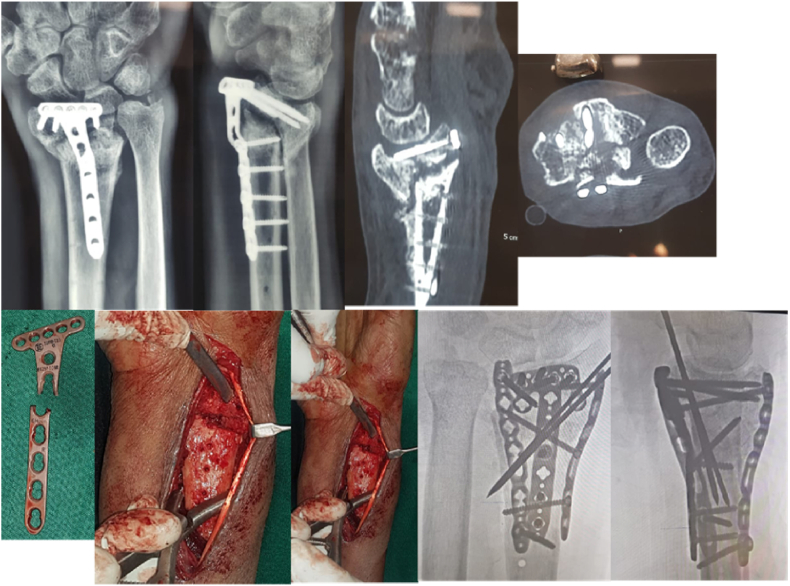

Case Example 1: Young male, non-dominant hand, fall while riding a bike, pre-operative CT showed incarcerated central depressed fracture with burst type fracture of distal radius, patient underwent ORIF with sandwich plating.

Case Example 2: Young male, dominant hand, presented with edematous, tender, stiff hand with deformity. Operated 6 weeks prior for same injury. Noticed deformity on removal of plaster and painful movement on physiotherapy. Pre-operative X-ray & CT revealed failed implant with screw in radiocarpal joint. Underwent Diagnostic arthroscopy to evaluate cartilage status, implant removal, ORIF with sandwich plating of volar, radial and dorsal columns with iliac crest bone graft.

Middle aged male, dominant hand, fall on outstretched hand, pre-operative imaging showed volar rim fracture. ORIF done with Synthes Rim plate to buttress the distal fragment.